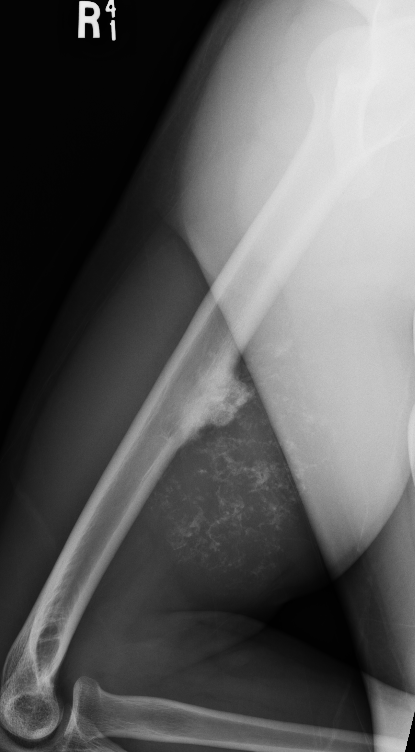

Large calcification with endosteal scalloping humerus

Large calcified lesion with endosteal scalloping